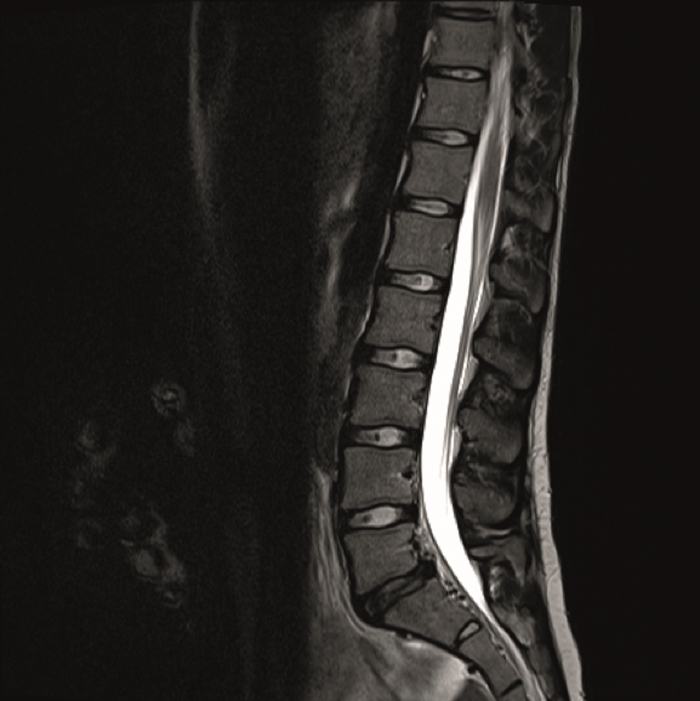

The preoperative standing image of the lumbar spine revealed a flat back with no obvious degeneration of the adjacent segment L1/L2 (Fig 6ab). The implants seemed regularly placed. After wide laminectomy, the spinal canal was open over the whole lumbar spine, illustrated on the MRI scan (Fig 6c).

A CT scan allowed a more detailed assessment (Fig 7). There was an obvious nonunion at L5/S1, with loose screws in the sacrum (red circle). Furthermore, there was instability at L4/L5 as the intervertebral disc presented with an important vacuum phenomenon (asterisk). Foraminal stenosis at L5/S1 (not shown) seemed to be the reason behind the persistent leg pain.